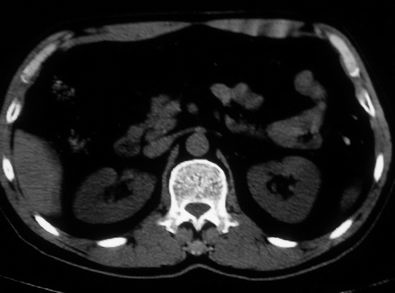

男,体查发现右肝低密度,右肾高密度结节影。高密度ct值92hu,囊肿?

肝右叶囊肿或血管瘤?右肾高密度囊肿。建议增强。

肝右叶圆形低密度灶,考虑囊肿或血管瘤,建议ct增强检查;右肾包膜下高密度圆形灶,考虑:囊肿并出血